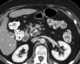

Mesenteric metastasis

Lymphadenopathy or adenopathy is a disease of the lymph nodes, in which they are abnormal in size or consistency. Lymphadenopathy of an inflammatory type (the most common type) is lymphadenitis, producing swollen or enlarged lymph nodes. [Source: Wikipedia ]